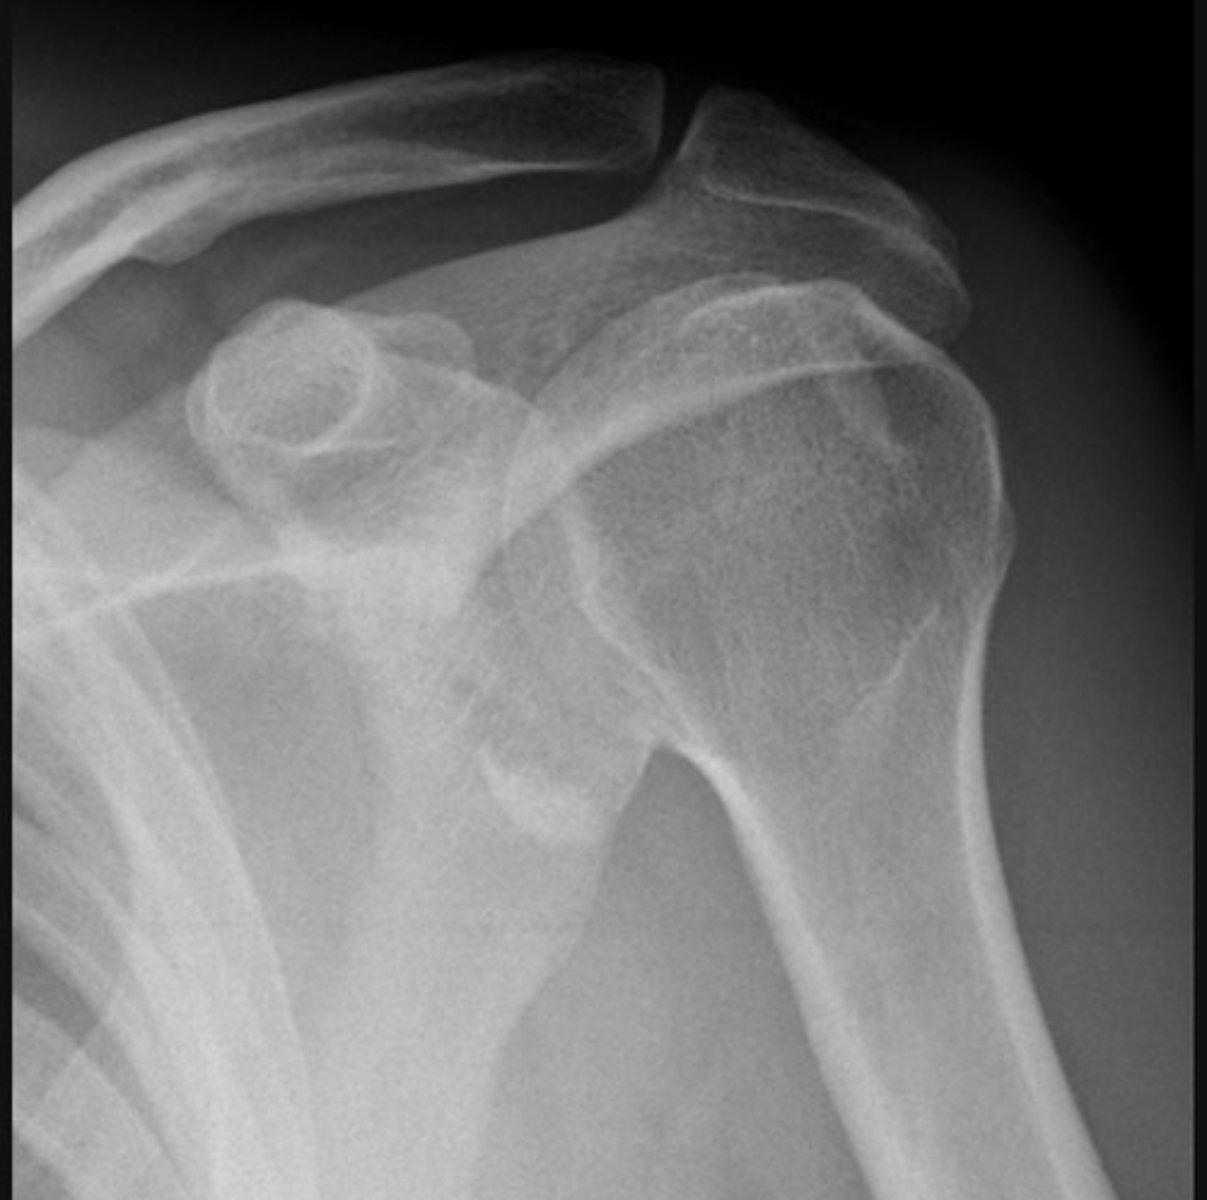

Anterior dislocation and Hill-Sachs lesion

Anterior dislocation and glenoid fracture (bankhart lesion)